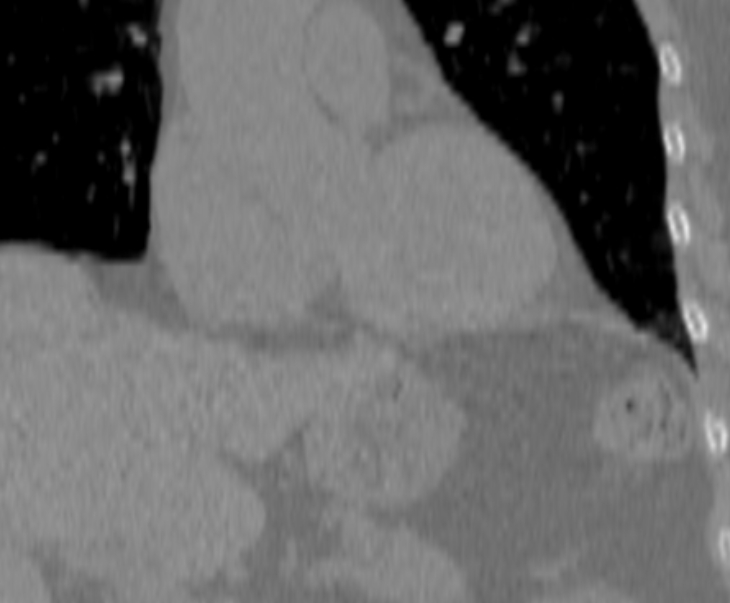

В нашей клинике исследование выполняется на новейшем 128-срезовом мультиспиральном компьютерном томографе экспертного класса TOSHIBA AQUILION CXL. Объектом данного исследования является сердце и коронарные артерии. Томограф производит послойное сканирование области сердца с шагом от 0,5 мм, и, благодаря высокой плотности отложения кальция и кальцинированные бляшки хорошо видны на снимках. За счет увеличенного количества сверхчувствительных детекторов сканирование происходит за несколько секунд, при этом доза рентгеновского облучения для пациента минимальна.

Для большей наглядности и определения точной локализации кальцинатов полученные при сканировании данные преобразуются аппаратом в объемные изображения сердца и сосудов.

Затем на основании полученных данных вычисляется индекс коронарного кальция (индекс Агатстона) для каждого коронарного сосуда в отдельности. Отсутствие кальция говорит о низком риске сердечно-сосудистых заболеваний.

Высокие показатели индекса кальция свидетельствуют о явном атеросклеротическом поражении коронарных артерий и образовании кальцинированных бляшек.